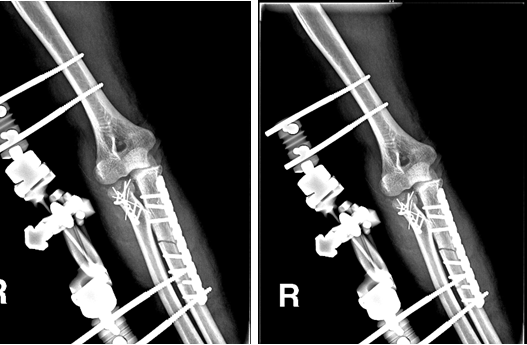

男性,22岁,摔伤致右肱骨髁间骨折

术前

术后